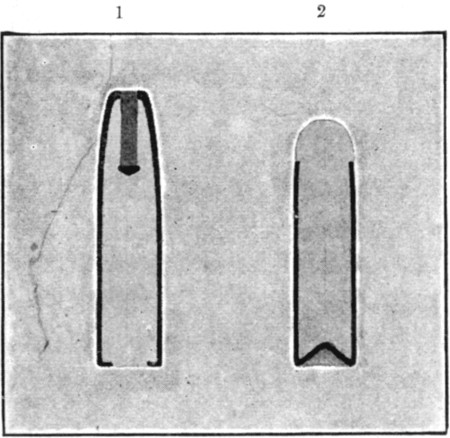

1. Section of Mauser Aperture of Entry To face p. 73

2. Section of Mauser Aperture of Exit 76

25a. Sections of Mauser Entry and Exit Wounds74